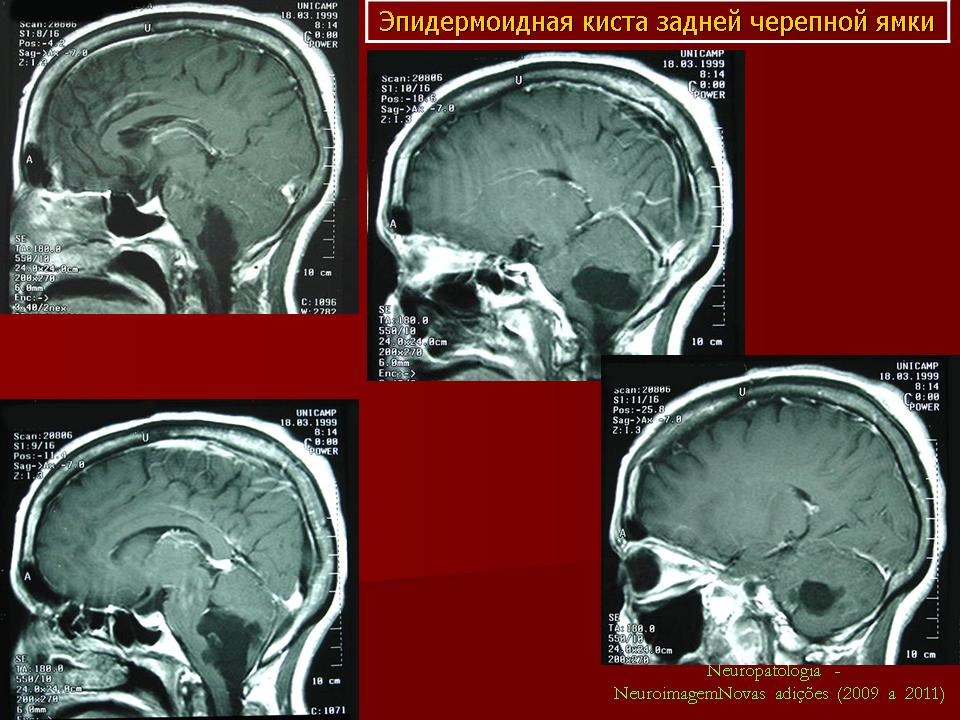

Эпидермоидные кисты задней черепной ямки

Эпидермоидные кисты задней черепной ямки - редкие новообразования. По данным Института нейрохирургии они составляют 0.5% от всех опухолей центральной нервной системы. Формирование морфологического субстрата эпидермоидных кист происходит на 3 неделе внутриутробной жизни, вследствие нарушения эмбриогенеза и смещения эпителиальной ткани в нервную трубку.

С 1985 по 2000 г.г. в НИИ нейрохирургии им. Н.Н. Бурденко обследовано и оперировано 78 больных с эпидермоидными кистами задней черепной ямки. Изучен клинический симптомокомплекс и КТ, МРТ картина эпидермоидных кист задней черепной ямки.

Качество оперативного лечения оценивалось изучением динамики неврологического статуса, данных КТ, МРТ, как до операции, так и после операции на разных его стадиях. Современные радиологические исследования и микрохирургическая техника полностью обеспечивает радикальное удаление эпидермоидных кист с хорошим после операционным результатом.